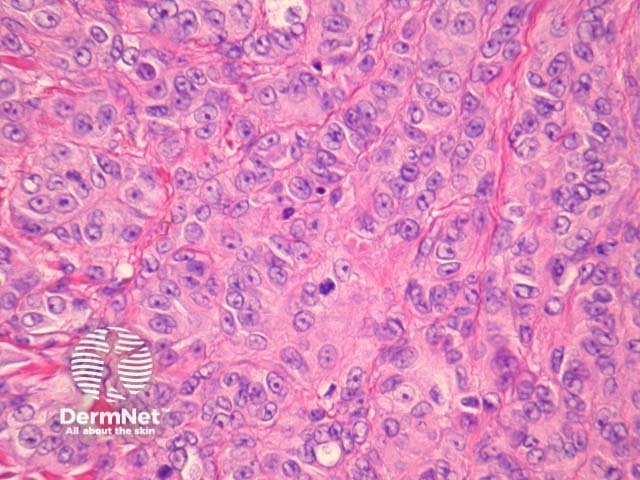

Cutaneous metastasis of melanoma can cause diagnostic confusion. The metastatic melanoma may invade the dermis or subcutis and form a nodular tumour mass without invasion of the overlying epidermis (figure 1). The pattern of growth may mimic a benign intradermal naevus at low power (figure 1) but at high power examination the nuclear atypia is usually obvious, there may be mitoses and there is minimal evidence of maturation (decrease in cell size) with descent in the dermis (figure 2). Usually the lack of epidermal involvement is a good clue the tumour is a metastasis from another site but sometimes the metastasis may invade the epidermis and closely simulate a primary melanoma.

Rarely, melanoma which has metastasised to the dermis may closely mimic a blue naevus (blue naevus-like melanoma, figures 3,4). This can cause considerable diagnostic difficulty and be impossible to correctly recognise without clinical information.